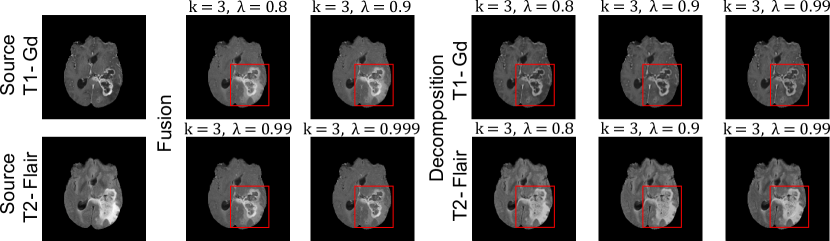

Refer to caption

Figure 4: Qualitative results of our FusionINN model at α=0.5𝛼0.5\alpha=0.5 and z𝒩(0,I)similar-to𝑧𝒩0𝐼z\sim\mathcal{N}(0,I).

3.0.4 Ablation Studies:

Table 2 demonstrates the impact of various parameters on FusionINN’s fusion and decomposition performance. The results indicate that three coupling blocks with λ=0.8𝜆0.8\lambda=0.8 and α=0.5𝛼0.5\alpha=0.5 produce competitive results in terms of QSSIMsubscript𝑄𝑆𝑆𝐼𝑀Q_{SSIM} scores. Additionally, increasing α𝛼\alpha enhances image fusion performance with respect to at least one source modality. We also explored different latent priors for z𝑧z, including learning zeros, ones and uniform distribution 𝒰[0,1)𝒰01\mathcal{U}[0,1). The results show that a normally distributed z𝑧z outperforms other settings, as it might contain more information about the data distribution than, for example, an image containing only zeros. In Fig. 4, the qualitative fusion and decomposition results convey that both λ=0.8𝜆0.8\lambda=0.8 and 0.90.90.9 prevents under-compensation of QSSIMsubscript𝑄𝑆𝑆𝐼𝑀Q_{SSIM} via 2subscript2\ell_{2} loss, resulting in superior visual quality.